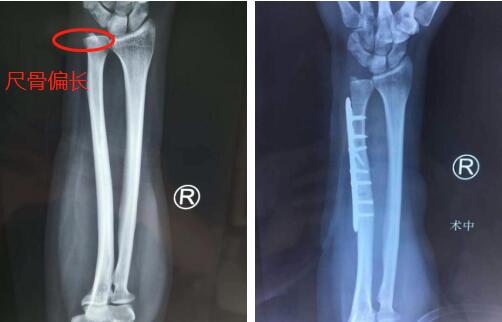

门诊病例:右尺骨撞击综合征,手术尺骨缩短截骨

40岁的张大姐是徐州沛县人,2019年12月的一天,她一早来到betway在线登陆手外科专家门诊室,见到了腕关节疾病专家齐伟亚主任。张大姐告诉齐主任,自己半年前摔倒过一次,当时右手掌撑地,右腕尺侧疼痛,在当地医院就诊后一直口服止痛药物治疗。最近两个月右腕尺侧疼痛加重,“拧毛巾”、“开门”时疼痛加重。齐主任为其安排专科检查,检查结果显示:右腕月骨、三角骨骨髓水肿,尺骨正变异,考虑右尺骨撞击综合征。

第二天,齐主任手术团队为张大姐进行了“腕关节镜辅助下右腕TFCC探查、滑膜清扫+尺骨缩短术”,尺骨远端斜行截骨3mm,复位后置入螺钉及钢板进行内固定,关节镜下探查并刨除腕关节内增生滑膜组织,手术顺利。

内固定

截骨(左图)手腕康复器材(右图)